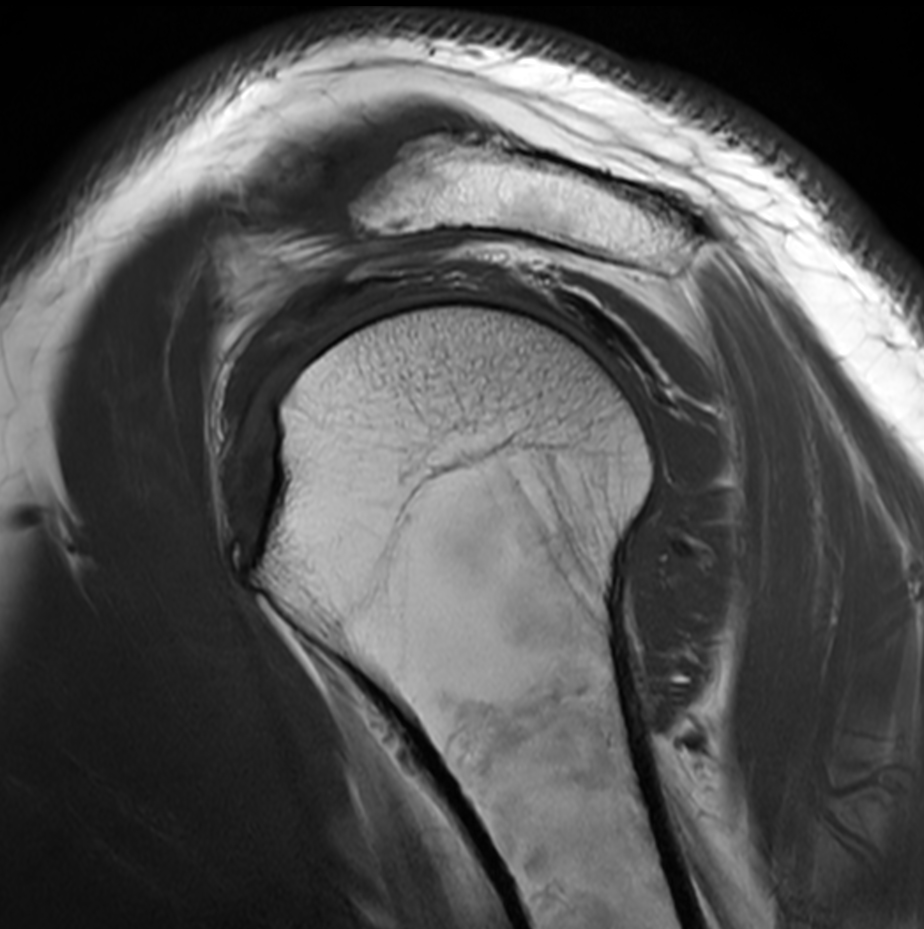

High resolution imaging with the dS 16ch Shoulder coil and Compressed SENSE